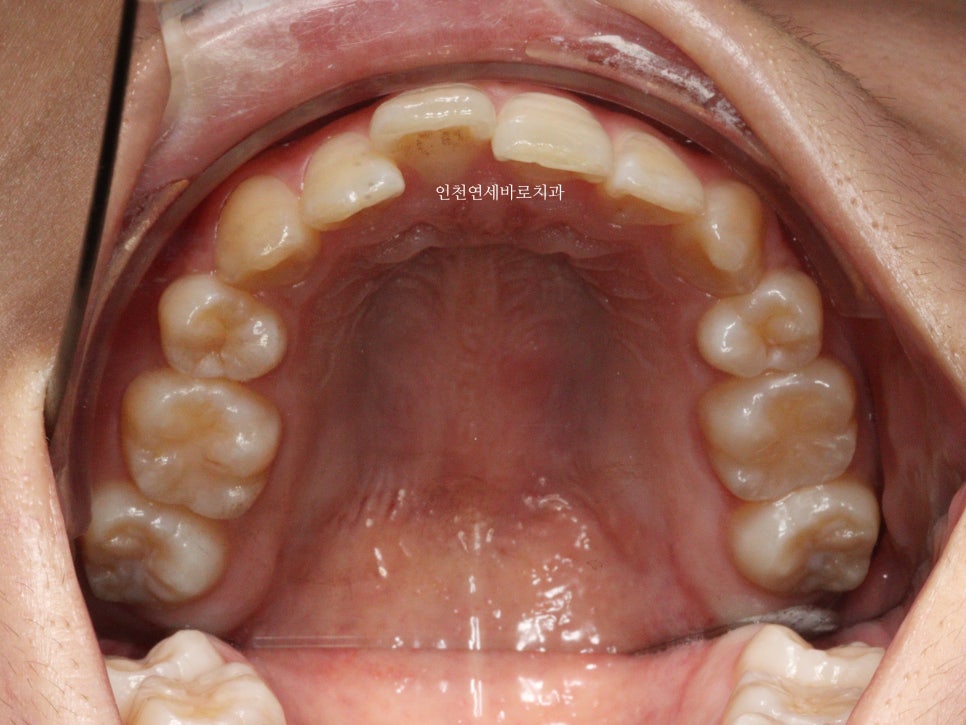

예전에 중학생때 발치교정치료를 받았다고 합니다.

이런 치열의 재교정은 거의 대부분의 환자분이 #부분교정 을 염두하시고 병원에 옵니다.

부분교정으로도 가능합니다.

하지만 부분교정과 인비절라인은 약간은 다른 개념이에요

부분교정은 부분만 바꾸는 교정치료이며,

인비절라인은 간단한 전체교정이라고 생각하면 됩니다.

인비절라인라이트 를 선택하셨어요.

부분교정으로 앞니만 철사를 붙여서도 비슷한 효과를 볼 수 있었을지 모릅니다.

하지만 치아의 삭제가 많은 양 동반되지 않았다면 앞니가 분명 뻗쳐나왔을것입니다.

하지만 인비절라인은 전체교정에 준하는

치아와 주변조직에 무리가 되지 않는 범위에서의 확장을 만들어낼 수 있어

앞니의 뻗침을 최소화 할 수 있는 장점이 있습니다.